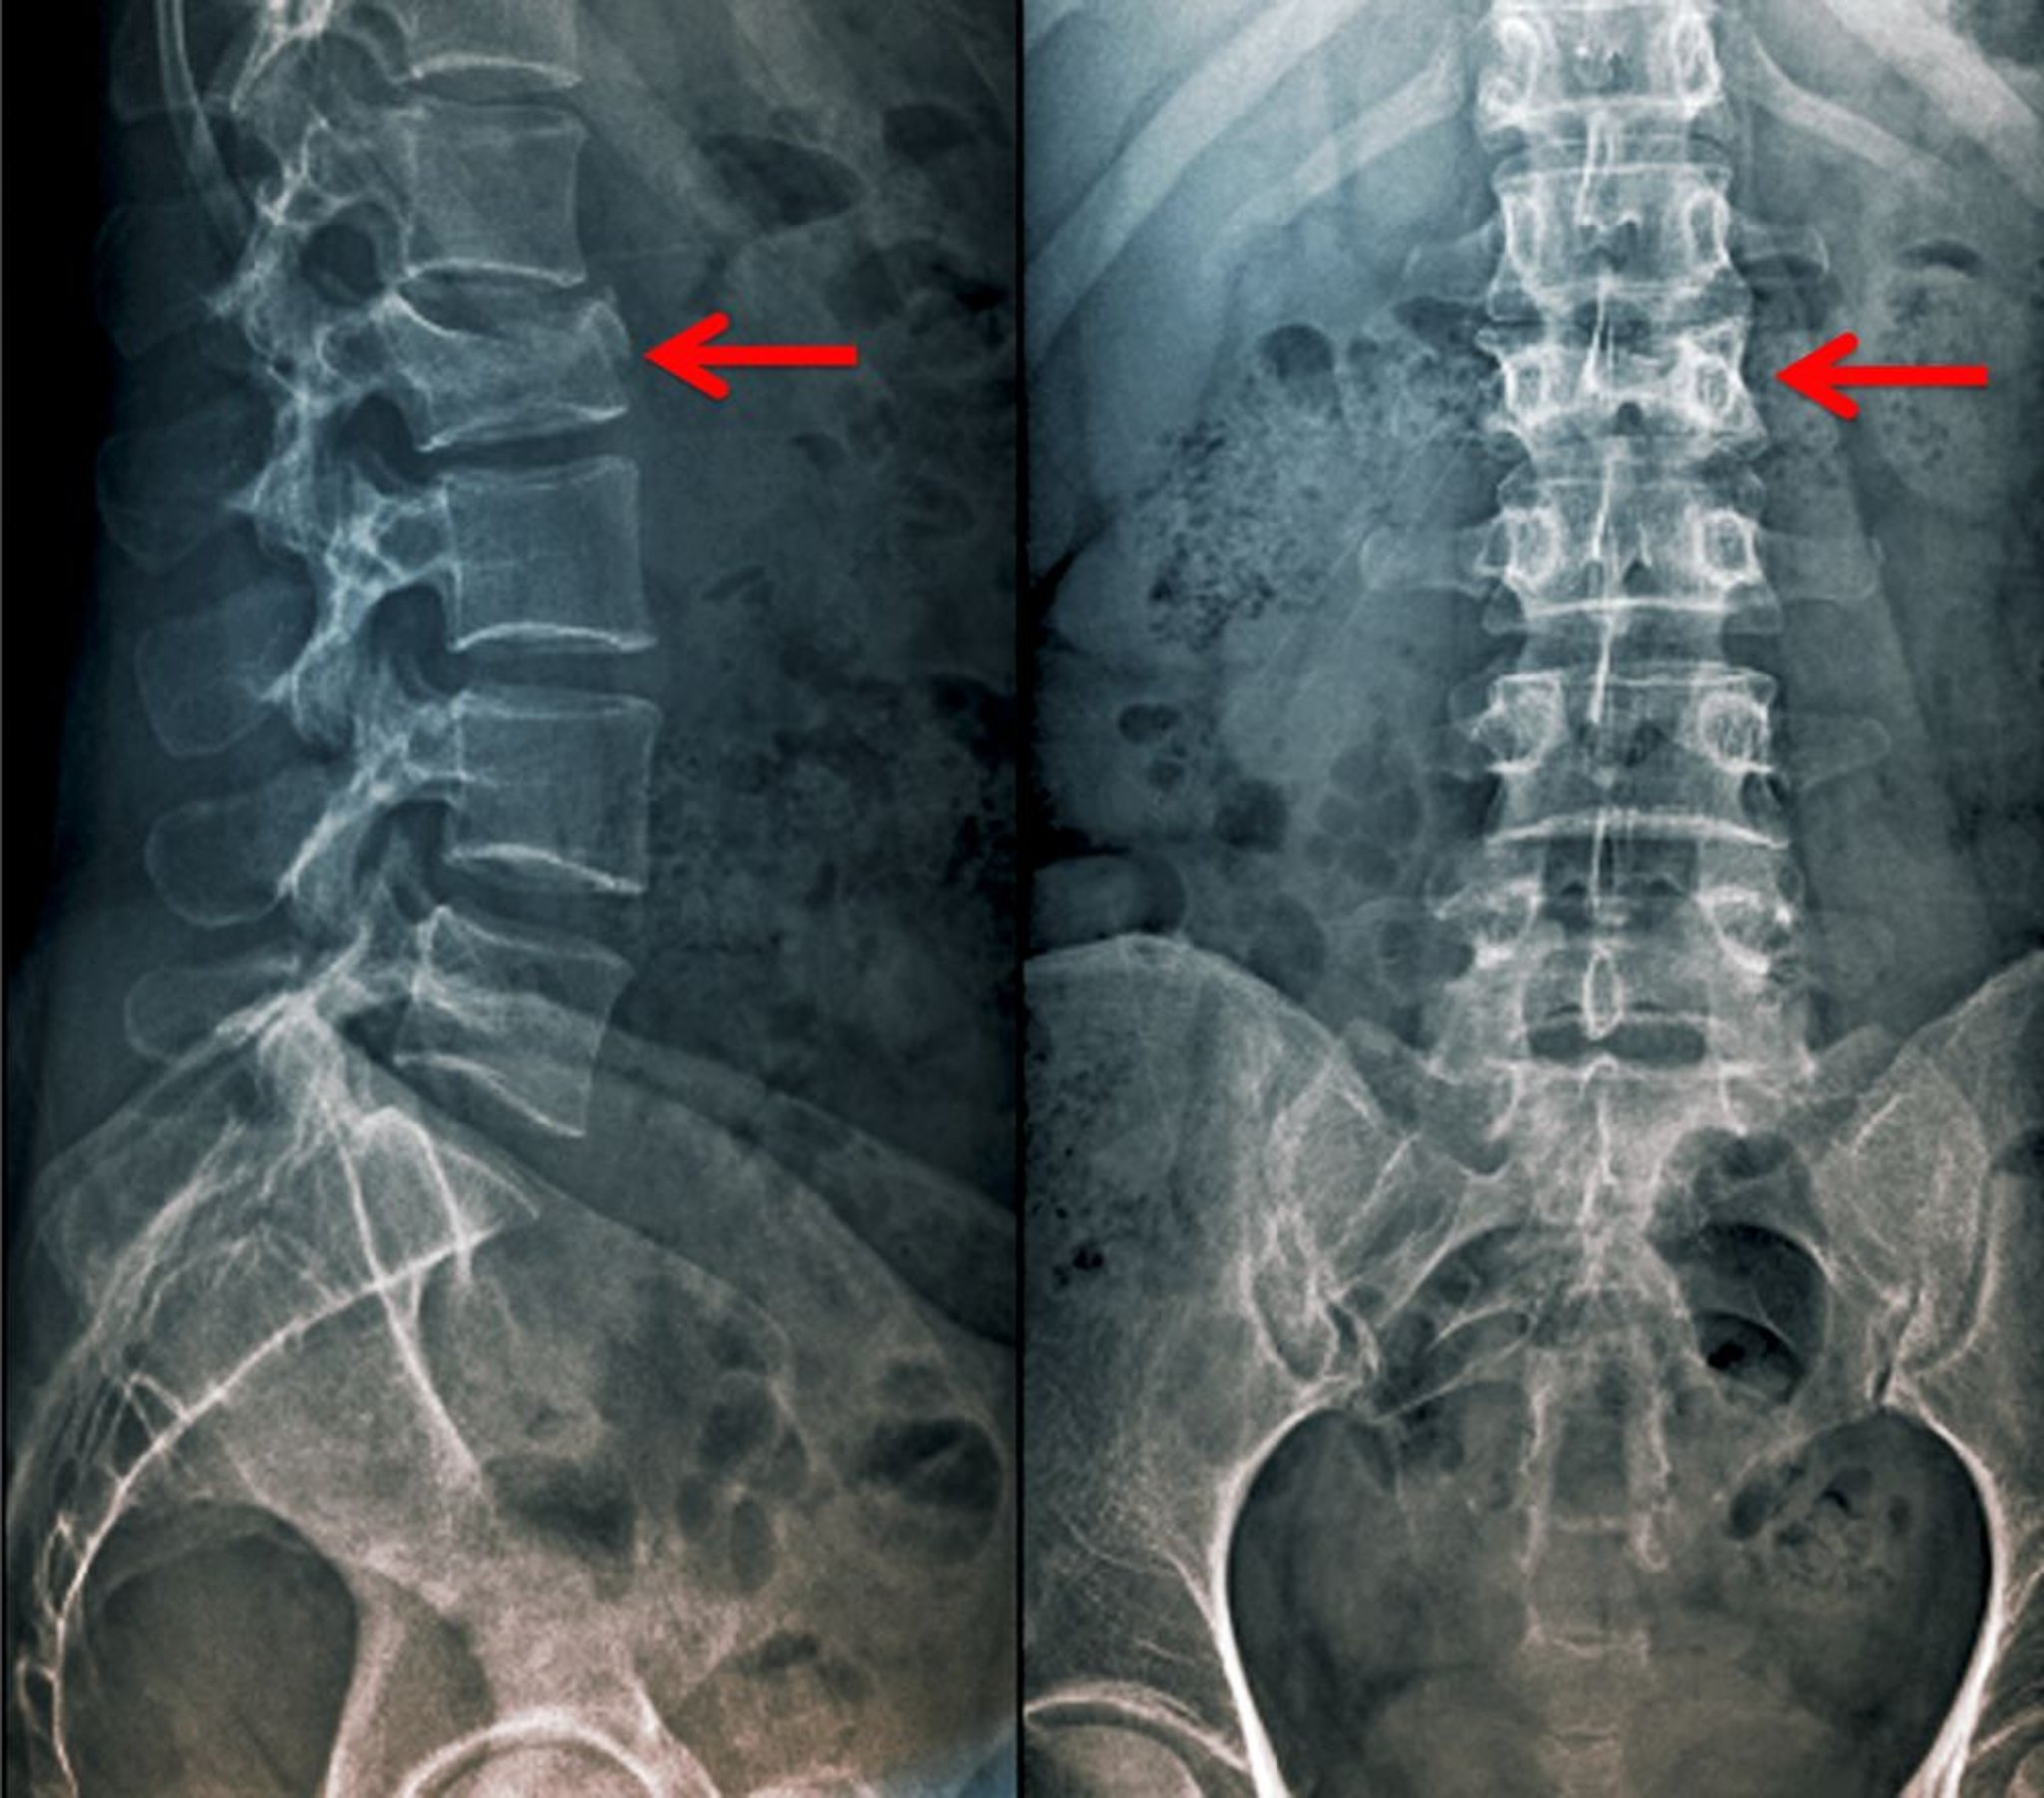

Компресійний перелом у передньо-задній та бічній проекціях

Зазначений компресійний перелом 2-го поперекового хребця проявляється як зменшення висоти тіла хребця в передньо-задній, а також у бічній проекціях.